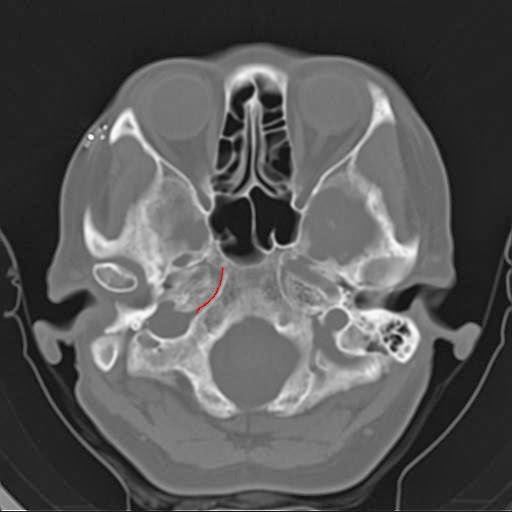

Рис. Расположение сигмовидного синуса (отмечен синим) и затылочно-сосцевидного шва (отмечен красным), заканчивающегося яремным отверстием (красный круг).

Рис. Расположение швов затылочной кости и смежных венозных синусов. SutPetroOcc - петро-базилярный шов, forJag - яремное отверстие, SutOccMast - затылочно-сосцевидный шов.

Хорошая подвижность в затылочно-сосцевидном шве и в следующих швах затылочной кости на основании черепа особенно важна для успешного дренирования крови по венозным синусам в яремную вену. Мы можем видеть, что сигмовидный синус проходит близко к вертикальной части затылочно-сосцевидного шва и лежит непосредственно под его горизонтальной частью. И как затылочно-сосцевидный шов заканчивается яремным отверстием и sutura petrojugularis, так и сигмовидный синус дренируется в яремную вену в яремном отверстии.